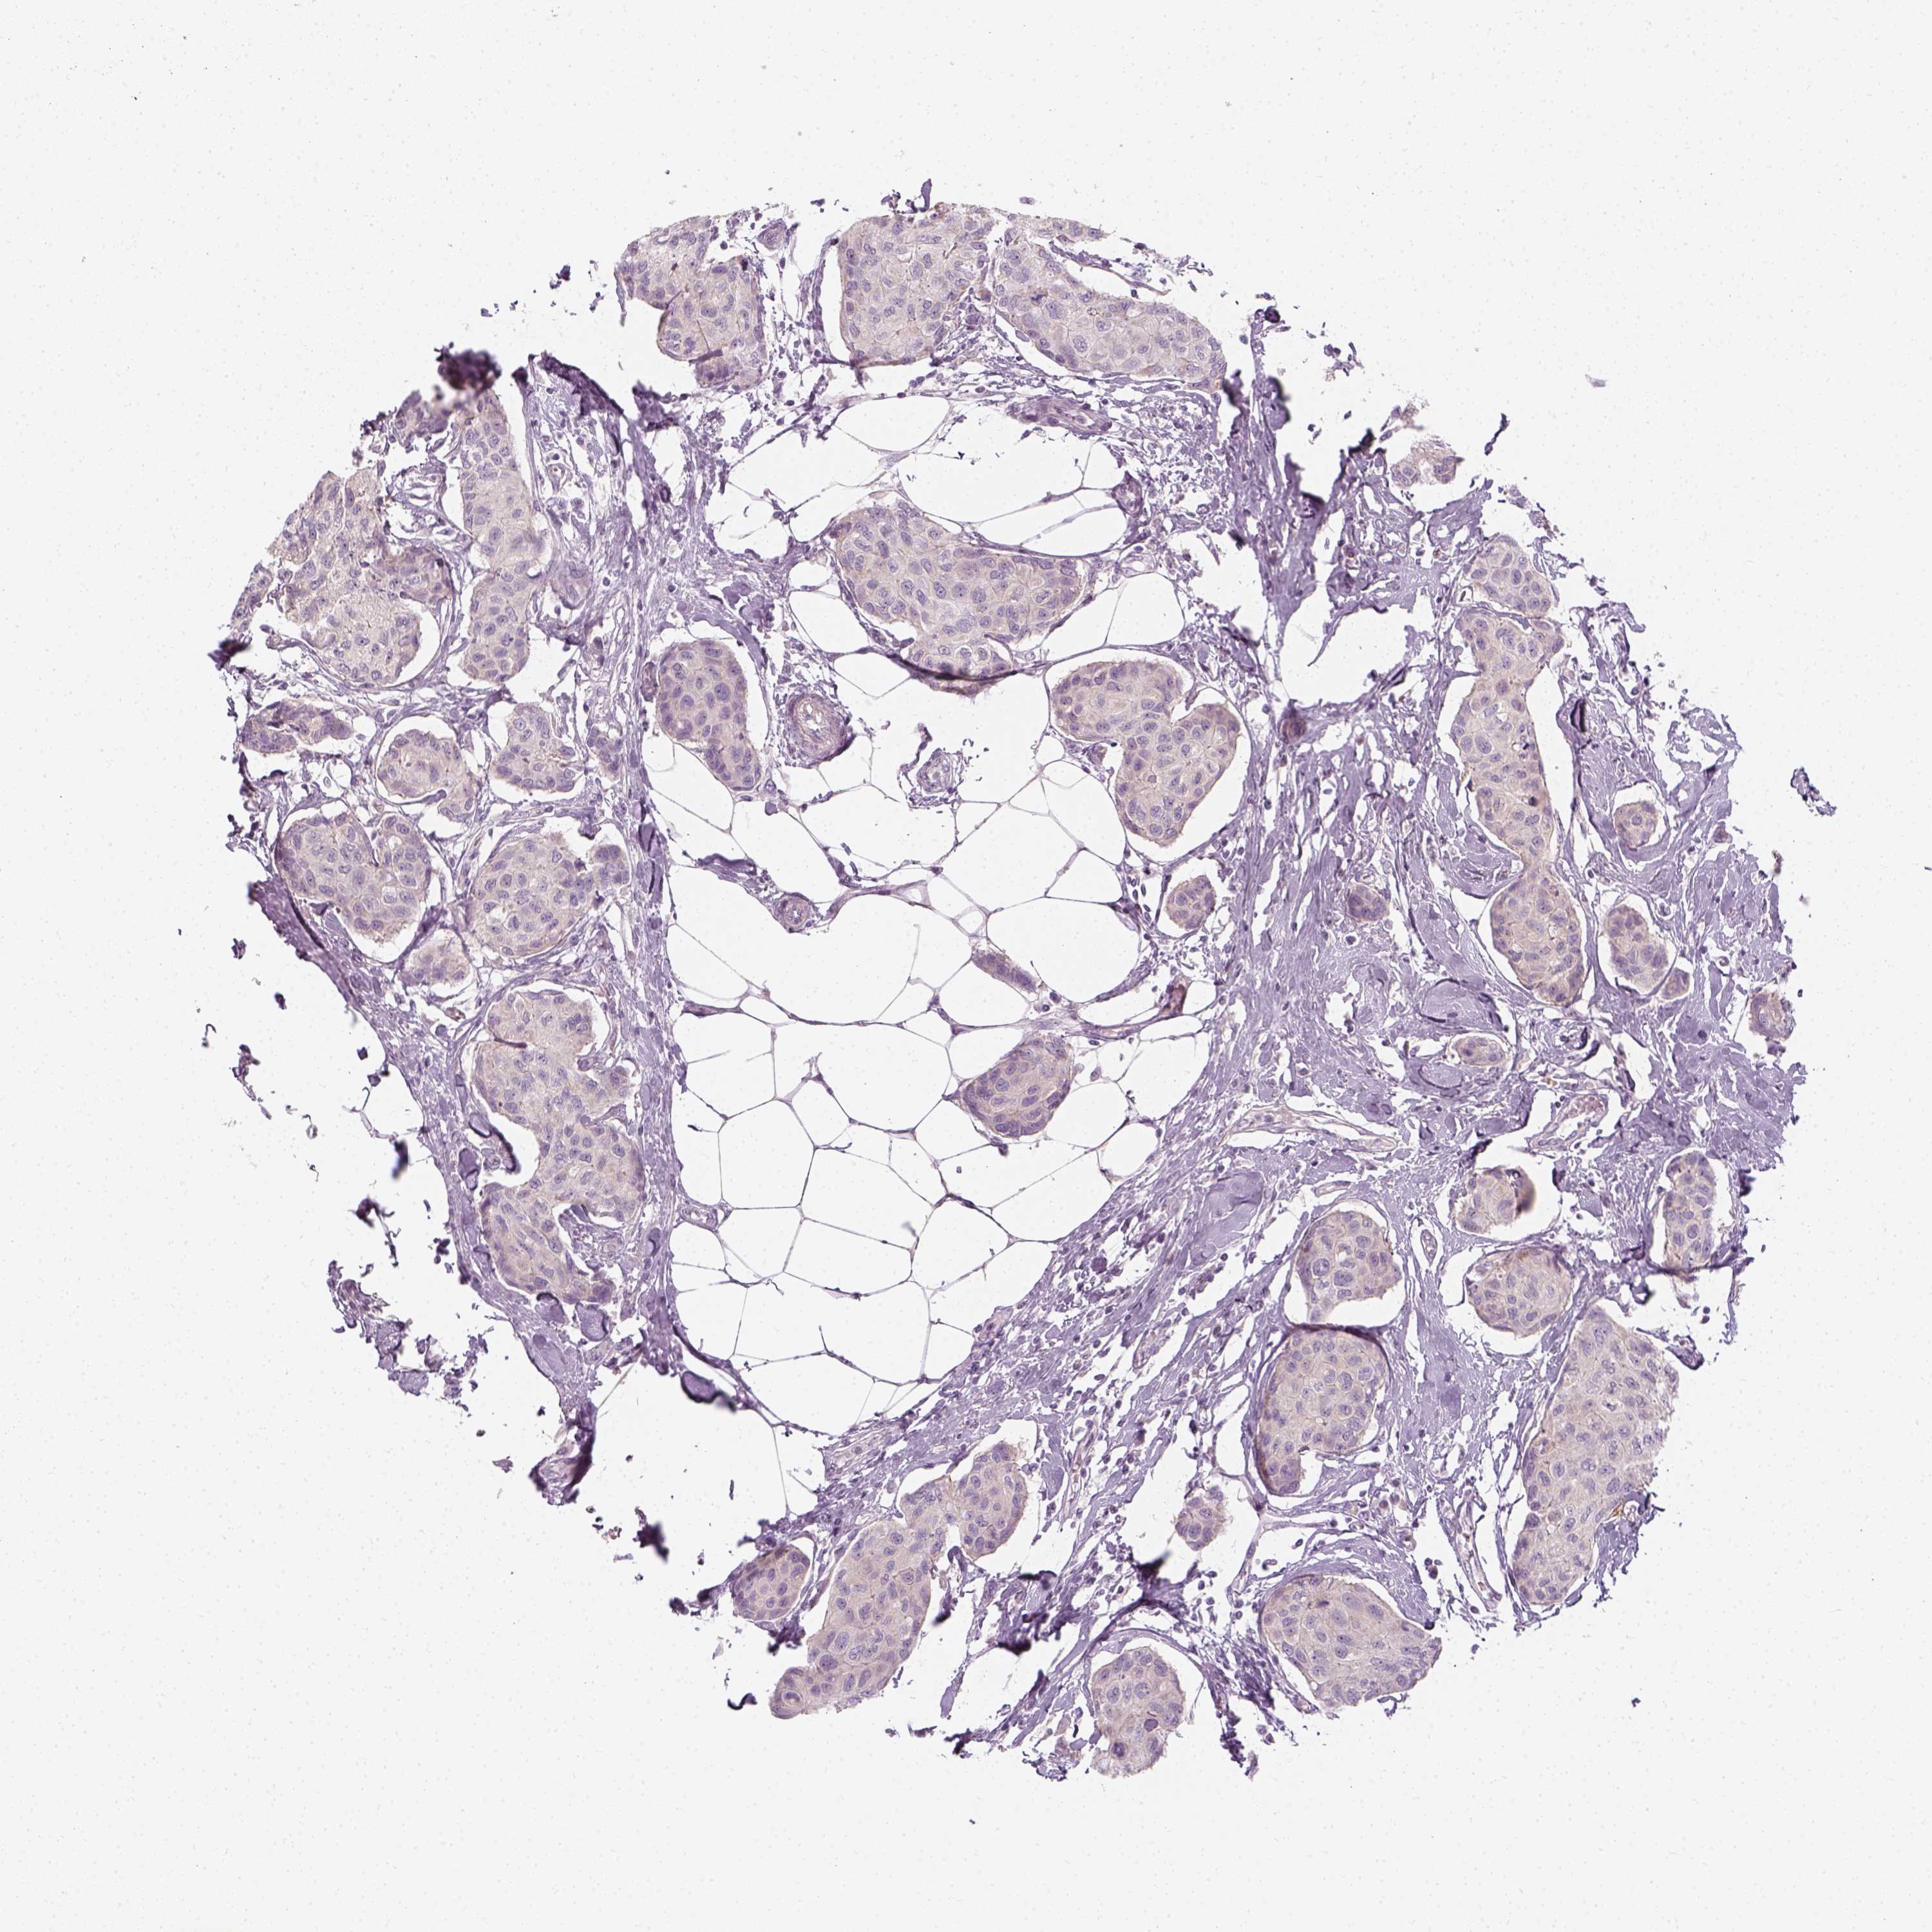

CANCER BREAST CANCER Show tissue menu

BRCA TCGA BRCA VALIDATION PROTEIN EXPRESSION